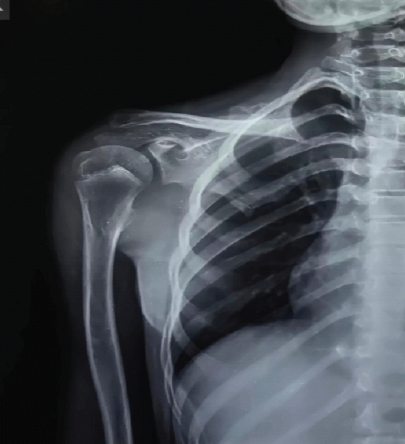

Histopathological examination confirmed benign osteochondroma. Post-operatively, the patient had significant improvement in shoulder mobility, with complete wound healing and no recurrence on follow-up examination and imaging(Figs. 5 and 6).

Figure 6: 1-year follow-up antero-posterior X-ray showing no recurrence of the lesion.